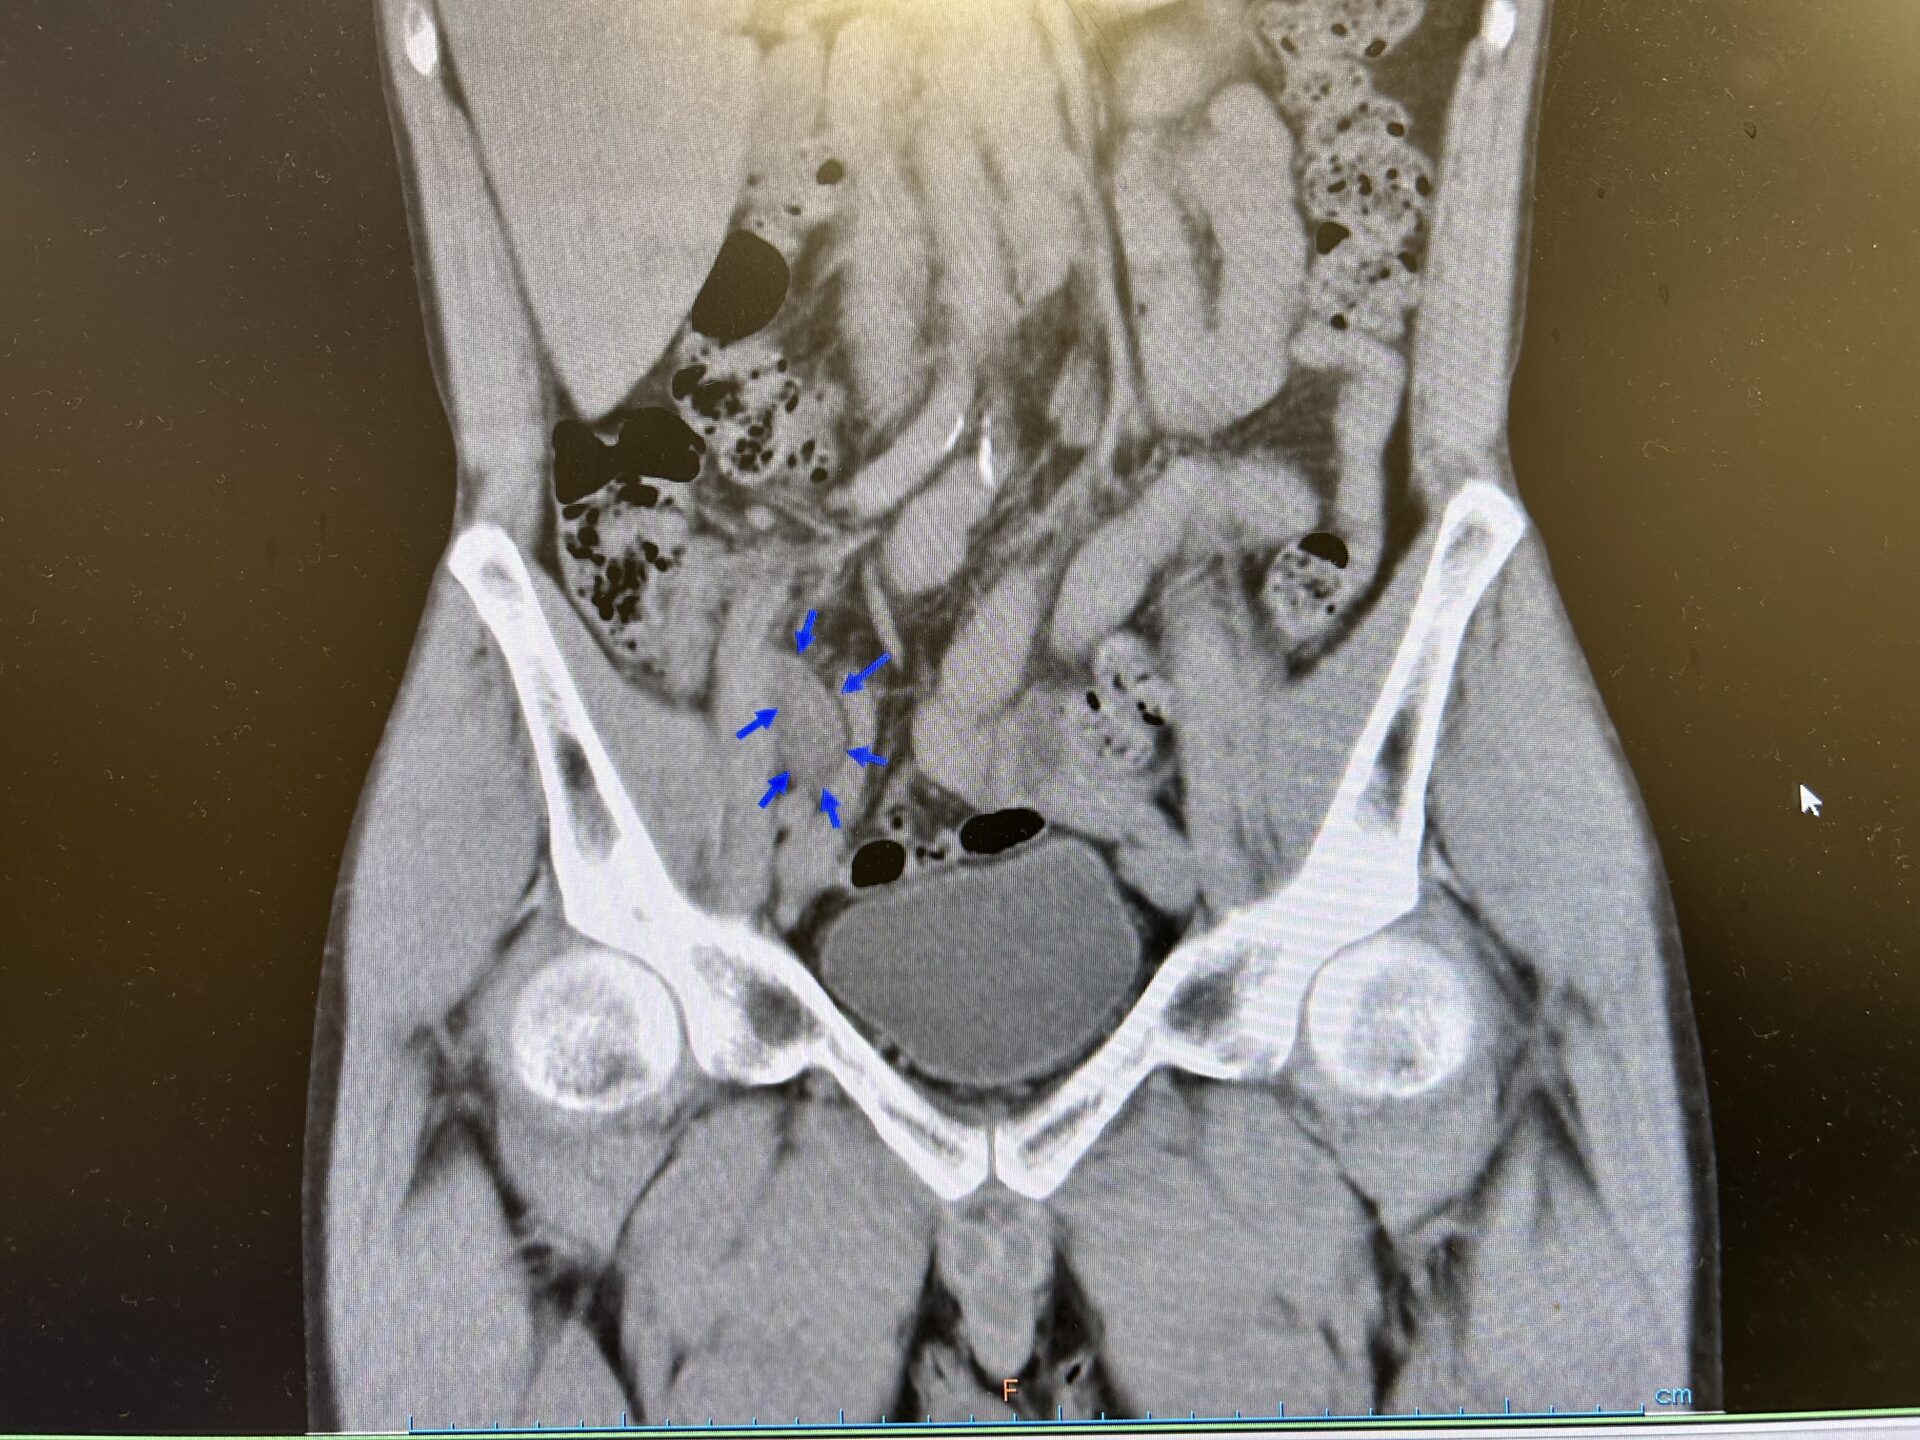

【緊急CT冠状断像:右下腹部に腫大した虫垂を認めている】

先ほどエコーで認められた虫垂の腫れた部位がやはりCT上でも同様の所見を認め、急性虫垂炎の診断が返ってきました。その後、患者さんには専門家に今後についてしっかりとコンサルトしましょうと説明し、近隣施設の消化器外科に緊急で紹介受診とさせていただきました。